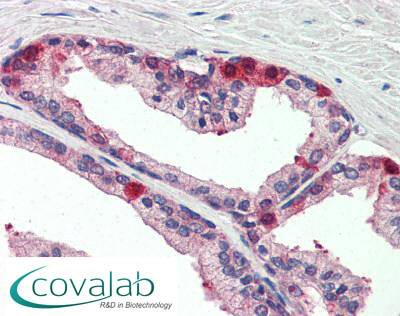

Anti-MARK3 antibody IHC staining of formalin-fixed, paraffin-embedded human small intestine after heat-induced antigen retrieval.

Anti-MARK3 antibody IHC staining of formalin-fixed, paraffin-embedded human small intestine after heat-induced antigen retrieval.